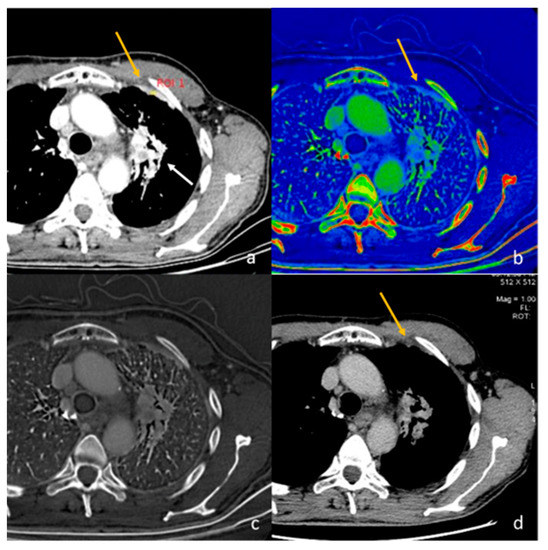

- Lennartz, S.; Le Blanc, M.; Zopfs, D.; Hokamp, N.G.; Abdullayev, N.; Laukamp, K.R.; Haneder, S.; Borggrefe, J.; Maintz, D.; Persigehl, T. Dual-Energy CT-derived Iodine Maps: Use in Assessing Pleural Carcinomatosis. Radiology 2019, 290, 796–804. [Google Scholar] [CrossRef]

- Poschenrieder, F.; Meiler, S.; Lubnow, M.; Zeman, F.; Rennert, J.; Scharf, G.; Schaible, J.; Stroszczynski, C.; Pfeifer, M.; Hamer, O.W. Severe COVID-19 pneumonia: Perfusion analysis in correlation with pulmonary embolism and vessel enlargement using dual-energy CT data. PLoS ONE 2021, 16, e0252478. [Google Scholar] [CrossRef] [PubMed]

- Idilman, I.S.; Dizman, G.T.; Duzgun, S.A.; Irmak, I.; Karcaaltincaba, M.; Inkaya, A.C.; Demirkazik, F.; Durhan, G.; Akpinar, M.G.; Ariyurek, O.M.; et al. Lung and kidney perfusion deficits diagnosed by dual-energy computed tomography in patients with COVID-19-related systemic microangiopathy. Eur. Radiol. 2021, 31, 1090–1099. [Google Scholar] [CrossRef]